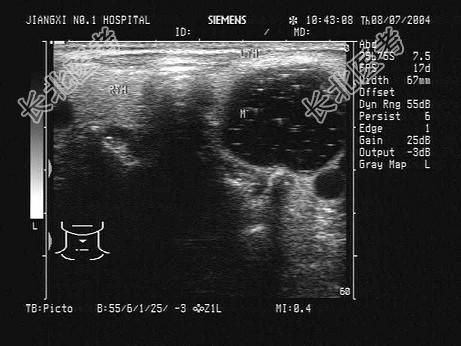

- 单项选择题患者,女, 25岁,颈部触及肿块半年余, 没有明显不适。甲状腺超声见右侧甲状腺一单发异常光团,如图。最可能的诊断为 ( )

A、甲状腺癌

B、甲状腺炎

C、甲状腺囊肿

D、结节性甲状腺肿

E、甲状腺腺瘤